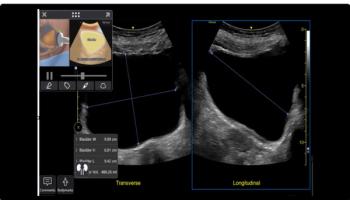

U-Systems’ somo •v Automated Breast Ultrasound (ABUS) system is approved for use in combination with mammography for women with dense breast tissue.

Ultrasound breast imaging uses a transducer to direct high-frequency sound waves throughout the breast. The uniquely-shaped somo•v Automated Breast Ultrasound system transducer scans the entire breast in approximately one minute and produces several images.